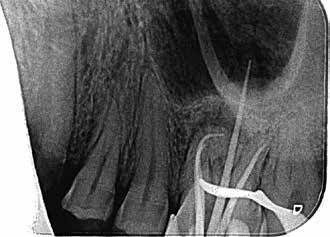

Bei der Diagnose des schmerzfreien Patienten stellte sich die beschriebene Erhebung schließlich als Fistel heraus (Abb. 1). Der Zahn 26 sowie die Nachbarzähne wurden zunächst einer Sensibilitätsprüfung unterzogen, wobei der Kältetest an Zahn 26 negativ ausfiel. Im Anschluss erfolgte dann die Anfertigung der diagnostischen Röntgenaufnahmen (Abb. 2 und 3). Dazu wurde ein Guttapercha-Stift in den Fistelgang eingebracht, um die Lokalisation der Entzündung zu erleichtern. Speziell bei der distal exzentrischen Aufnahme ließ sich dabei an 2 Wurzelspitzen des Zahns 26 die Entzündung ausmachen (Abb. 2). Insofern war in diesem Fall eine endodontische Behandlung des Zahnes angezeigt. Für diese wurde sogleich ein Folgetermin vereinbart.